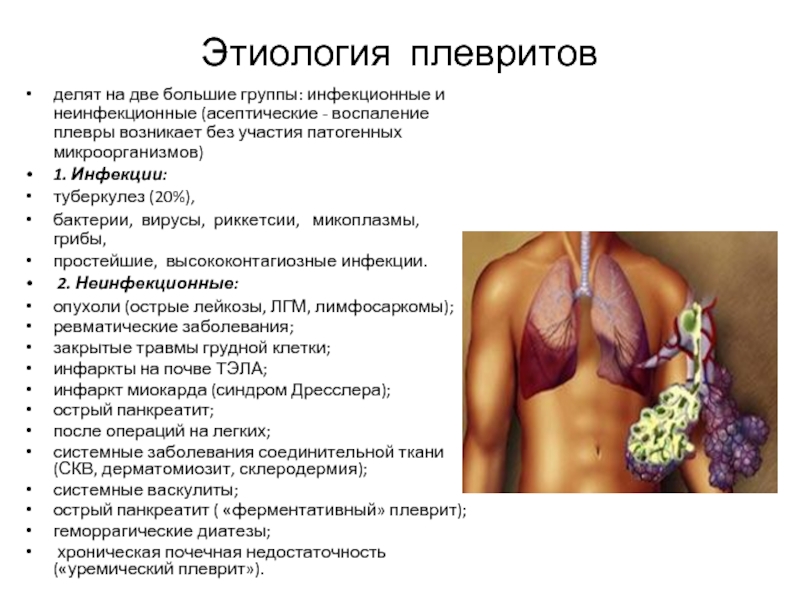

Дифференциальная диагностика заболеваний плевры